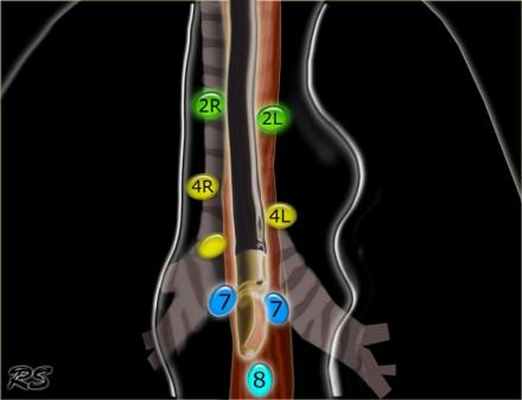

Верхние медиастинальные лимфатические узлы 2-4

2L Левые верхние паратрахеальные располагаются вдоль левой стенки трахеи, от верхнего края рукоятки грудины до верхнего края дуги аорты.

2R Правые верхние паратрахеальные располагаются вдоль правой стенки трахеи и спереди от трахеи до ее левой стенки, с уровня верхнего края рукоятки грудины до нижней стенки левой плечеголовной вены в зоне пересечения с трахеей.

4R Нижние паратрахеальные от пересечения нижнего края плечеголовной вены с трахеей до нижней границы непарной вены, вдоль правой стенки трахеи до ее левой стенки.

4L Нижние паратрахеальные от верхнего края дуги аорты до верхнего края левой главной легочной артерии

Нижние медиастинальные лимфатические узлы 7-9

7. Подкаринальные лимфатические узлы.

8. Параэзофагеальные лимфатические узлы. Лимфатические узлы ниже уровня карины.

4R. Правые нижние паратрахеальные лимфатические узлы

Верхняя граница: пересечение нижнего края левой плечеголовной вены с трахеей.

Нижняя граница: нижний края непарной вены.

4R узлы распространяются до левого края трахеи.

4L. Левые нижние паратрахеальные лимфатические узлы

4L узлы расположенные слева от левой стенки трахеи, между горизонтальными линиями проведенными касательно верхней стенке дуги аорты и линией проходящей через левый главный бронх на уровне верхнего края верхнедолевого бронха. Они включают паратрахеальные узлы расположенные кнутри от артериальной связки.

7. Подкаринальные лимфатические узлы

Эти лимфатические узлы расположены ниже уровня бифуркации трахеи (карины), но не относятся к нижнедолевым бронху и артерии. Справа они располагаются каудальнее нижней стенки промежуточного бронха. Слева они располагаются каудальнее верхней стенки нижнедолевого бронха.

8. Параэзофагеальные лимфатические узлы

Эти лимфатические узлы ниже подкаринальных лимфатических узлов и распространяются каудальнее до диафрагмы.